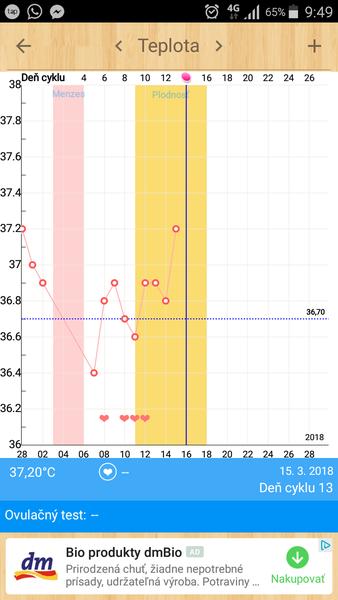

Grafy bazálnej teploty

Baby, nová téma o grafoch BT, ovulačných testoch, tehotenských testoch a hľadaní duchov je tu 🙂

Ak meriate bazálnu teplotu a zapisujete si hodnoty do grafov, ste na správnom mieste. Poradíme, pomôžeme, podporíme.

Babulky moje,dnes poobede ako som bola na wc tak na spodnom prádle som mala hnedé spinenie.a celkom dost.ale na toaletnom vobec nic.ani teraz.neviete co to moze prosim byt?? Dakujeem.grafik mam vysie.

@dadulik6 aha Dakujeem moje 🙂 len prvy krát v živote to mam 🙂 ze pri ovu.noo fasa.dnes sme nepoistili☹ poobede sme obaja zaspali a muzik isiel na nočnú ☹ uvidim aka bude teplotka rano🙂 uz by sa nam zlatik mohlo aj šťastie na nas usmiat.ze??:-(